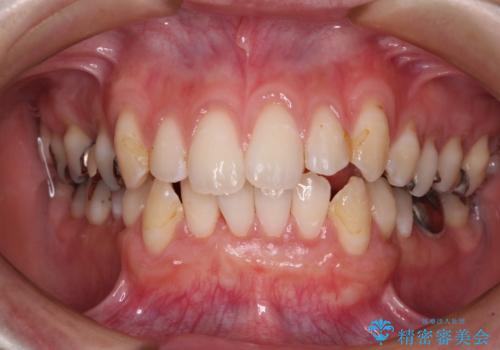

歯肉退縮に対して、上顎からの結合組織移植術(CTG)により、歯根の被覆を行うとともに、歯肉の厚みを増すことで将来の退縮リスクを抑制することとしました。

上顎両側から歯肉を採取したたため、術後は痛みや出血で辛い思いをされましたが、1回の処置で満足のいく結果となりました。